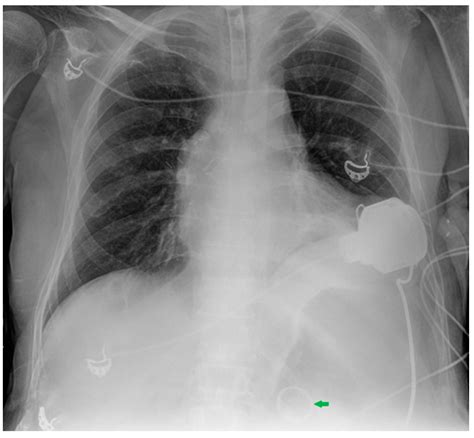

Chest X-ray Interpretation: Detecting Devices and Device-Related ...